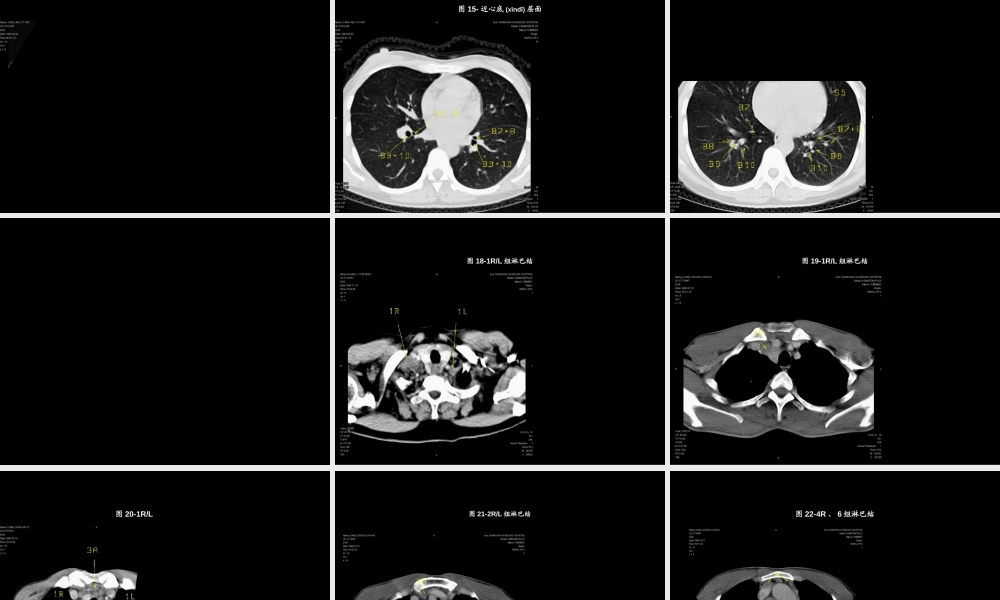

图1-16:正常胸部断层(duàncéng),图1-胸锁关节(guānjié)层面第一页,共八十一页。图2:主动脉弓(zhǔdòngmàigōng)层面ARCH:主动脉弓(zhǔdòngmàigōng)第二页,共八十一页。Az:奇静脉(jìngmài)弓B1:上叶尖段支气管S3:上叶前段图3-主肺动脉窗层面第三页,共八十一页。图4-奇静脉(jìngmài)弓层面S6:下叶背段第四页,共八十一页。图5-近隆突层面B1+2:左上叶尖后段支气管B3:上叶前段支气管第五页,共八十一页。图6-隆突层面第六页,共八十一页。图7-隆突下1cm层面Bi:中间(zhōngjiān)支气管第七页,共八十一页。图8-隆突下1cm层面LUMB:左上叶支气管第八页,共八十一页。图9-隆突下2cm层面V3:上叶前段静脉(jìngmài)的段间支第九页,共八十一页。图10-隆突下2cm层面S4:右中叶(zhōngyè)外段/左舌上段第十页,共八十一页。图11-隆突下3cm层面B4:右中叶(zhōngyè)外侧段/左舌上段支气管第十一页,共八十一页。图12-隆突下3cm层面B6段第十二页,共八十一页。图13-隆突下3cm层面第十三页,共八十一页。图14-近心底(xīndǐ)层面5右侧段/段第十四页,共八十一页。图15-近心底(xīndǐ)层面B7+8:下叶前内段支气管第十五页,共八十一页。图16-近心底(xīndǐ)层面B段第十六页,共八十一页。图17-锁骨(suǒgǔ)上和斜角肌组淋巴结应扫描从锁上膈上锁上和斜第十七页,共八十一页。图18-1R/L组淋巴结肺臂静脉横入右臂静第十八页,共八十一页。图19-1R/L组淋巴结第十九页,共八十一页。图20-1R/L、3A/P组淋巴结肺动脉上缘层前组组第二十页,共八十一页。图21-2R/L组淋巴结侧淋右/第二十一页,共八十一页。图22-4R、6组淋巴结位于主动脉弓(zhǔdòngmàigōng)上缘以下主动脉、主动脉弓前方及两侧的淋巴结-为升主动脉旁组(6组)第二十二页,共八十一页。图23-4R/L、6组淋巴结还可静脉界将右侧4组第二十三页,共八十一页。图24-4R/L、5、6组淋巴结淋-动脉或第二十四页,共八十一页。图25-7组淋巴结组第二十五页,共八十一页。图26-7、10R组淋巴结淋-右/肺组第二十六页,共八十一页。图27-8、10R/L组淋巴结右/8R/L组第二十七页,共八十一页。图28-9、11R组淋巴结肺静脉周淋第二十八页,共八十一页。图29-12、13、14R/L组淋巴结邻近各肺段淋第二十九页,共八十一页。图30-肺间质病变(bìngbiàn)常规(chángguī)或标准CT扫描、重建第三十页,共八十一页。图31-肺间质病变(bìngbiàn)建第三十一页,共八十一页。图32-肺间质病变(bìngb...